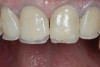

(13.) Postoperative occlusal view of upper arch.

Figure 13

After the composite veneers were finalized, impressions were taken for a monolithic lithium disilicate crown on tooth No. 12. This was placed during a subsequent appointment, and occlusal equilibration was carried out. The patient returned for final photographs a couple of weeks later (Figure 10 through Figure 14).

At the initial appointment, all of the patient's carious lesions were treated, and tooth No. 12 was fitted with a provisional crown made from a bis-GMA temporary material. At the next appointment, the patient's tissues were anesthetized, and the posterior teeth were isolated with a rubber dam in quadrants. The teeth were cleaned with air abrasion and etched with phosphoric acid. Studies have shown that air abrasion using 27 µm aluminum oxide at 40 psi greatly improves bond strength when compared with cleaning tooth surfaces using hand instruments, a slurry mixture of pumice and water, or air abrasion using 50 µm aluminum oxide at 40 psi.19 After silane and a bonding agent were applied, the onlays were loaded with a flowable composite and individually cemented (Figure 6). Minimal occlusal adjustments were then carried out to ensure simultaneous posterior contacts.

During subsequent appointments, teeth Nos. 4 through 13 were restored with direct composite veneers in stages. Teeth Nos. 6 through 12 were treated first, followed by teeth Nos. 4, 5, and 13, respectively. Lingual and facial silicone putty indices were fabricated from the wax-up (Figure 7), and the lingual matrix was marked with a sharp probe at the existing incisal edge. Next, low-pressure air abrasion was used to clean the area and roughen the enamel to be bonded. Teeth Nos. 4 and 12 were isolated using polytetrafluoroethylene plumber's tape, and a 37.5 % phosphoric acid etching gel was applied and rinsed off. A layer of a fifth-generation bonding agent was applied and air-thinned, then a second layer was applied, air-thinned, and cured. The application of two layers has been shown to produce an increase in microtensile bond strength.20 After placement of the bonding agent, a clear enamel shade of microhybrid composite was applied into the lingual matrix in a thin layer and drawn slightly over the previously marked line. The composite was thickened toward the facioincisal line angle, which creates a natural "halo effect." The matrix was then adapted to the teeth, and the lingual shelf was briefly cured (Figure 8).